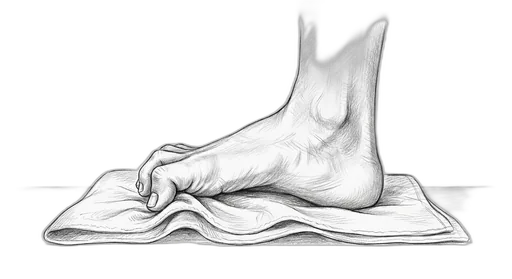

Towel Curl

This exercise strengthens the small muscles on the bottom of your foot — called the intrinsic foot muscles. These are the muscles that support your arch from the inside, kind of like a built-in orthotic. When they're strong, they help distribute your body weight more evenly, protect against overpronation (your foot rolling inward too much), and take stress off the plantar fascia, tendons, and joints.

What to expect: You may not feel dramatic changes in the first few weeks, but stick with it — these small muscles take time to build. By 6–8 weeks, many patients notice better arch support, less foot fatigue at the end of the day, and improved balance. The research shows measurable strength gains by 4–6 weeks.

How to do it: Sit in a chair with your bare feet flat on the floor. Lay a small towel flat under your foot. Curl your toes to scrunch the towel toward you — like you're trying to pick it up with your toes — then spread your toes flat and repeat. Try to use all five toes, not just the big one.

| Level | Hold | Reps | Sets | How Often | Tips |

|---|---|---|---|---|---|

| Mild | 3–5 sec per curl | 10 | 3 | 1×/day | Focus on curling with all your toes evenly — it takes practice, and that's okay |

| Moderate | 3 sec per curl | 8 | 2 | 1×/day | Use a thin towel on a smooth floor to make it easier |

| Severe | 2 sec per curl | 5 | 1 | 1×/day | If the towel is too hard, just practice curling your toes on carpet without it |

How to progress: Start with a thin towel on a smooth floor → thicker towel → place a small water bottle at the far end of the towel for added resistance. When seated feels easy, try it standing.

⚠ When to skip this: Hold off if you're recovering from hammertoe surgery or an acute plantar plate tear (first 4 weeks). Your surgeon will let you know when it's safe to start.